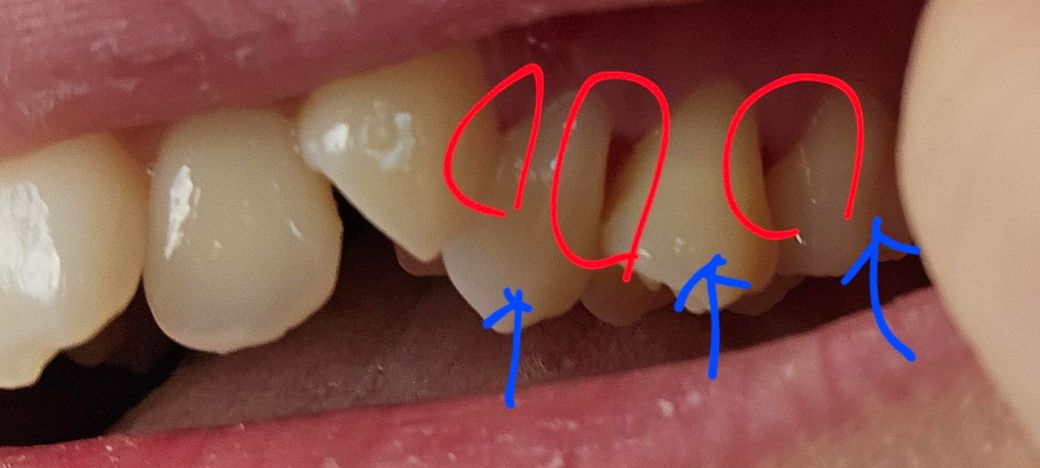

치경부마모증으로 레진치료 12일 후 레진치료한 어금니 3개 사이에 위치한 잇몸이 욱신거리고 치실할때마다 피가 납니다.

해당부위가 욱신거리고 치실할때마다 피난다..

• 1번 째 사진